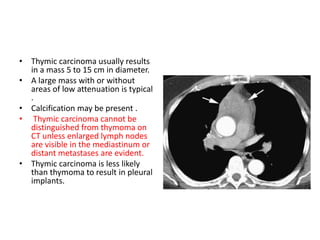

• Thymic carcinoma usually results

in a mass 5 to 15 cm in diameter.

• A large mass with or without

areas of low attenuation is typical

• Calcification may be present .

• Thymic carcinoma cannot be

distinguished from thymoma on

CT unless enlarged lymph nodes

are visible in the mediastinum or

distant metastases are evident.

• Thymic carcinoma is less likely

than thymoma to result in pleural

implants.

• Thymic carcinomausually results in a mass 5 to 15 cm in diameter. • A large mass with or without areas of low attenuation is typical . • Calcification may be present . • Thymic carcinoma cannot be distinguished from thymoma on CT unless enlarged lymph nodes are visible in the mediastinum or distant metastases are evident. • Thymic carcinoma is less likely than thymoma to result in pleural implants.